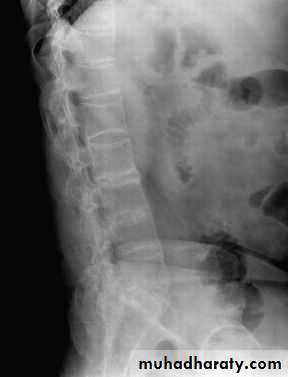

In established AS, radiographs of the sacroiliac joint show irregularity and loss of cortical margins, widening of the joint space and subsequently sclerosis, joint space narrowing and fusion.Lateral thoracolumbar spine Xrays may show anterior ‘squaring’ of vertebrae due to erosion and sclerosis of the anterior corners and periostitis of the waist.

Bridging syndesmophytes may also be seen. These are areas of calcification that follow the outermost fibres of the annulus

Investigations

In advanced disease, ossification of the anterior longitudinal ligament and facet joint fusion may also be visible. The combination of these features may result in the typical ‘bamboo’ spine.Erosive changes may be seen in the symphysis pubis, the ischial tuberosities and peripheral joints.